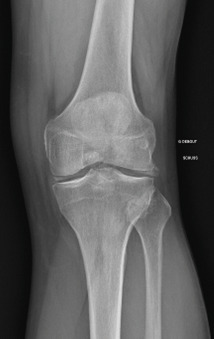

La forme pseudorhumatoïde est rare (5 %), simulant une polyarthrite rhumatoïde. L’arthrite chronique à PPC se présente comme une oligo- ou une polyarthrite, avec parfois des signes systémiques d’inflammation (élévation de la vitesse de sédimentation et de la protéine C-réactive [CRP]). La superposition d’accès aigus microcristallins est évocatrice de ce diagnostic. Il s’agit d’un diagnostic différentiel de polyarthrite rhumatoïde du sujet âgé ou de pseudopolyarthrite rhizomélique. Le diagnostic repose sur la mise en évidence des cristaux de PPC, même si les radiographies standard sont évocatrices. L’atteinte radiographique associe des calcifications des cartilages articulaires (fig. 7) et des fibrocartilages (fig. 8, 9, 10 et 11) [à rechercher systématiquement sur les radiographies de poignets, genoux et symphyse pubienne]. La mise en évidence d’une chondrocalcinose sur des radiographies standard renforce le diagnostic de rhumatisme à PPC mais l’absence de dépôts calciques ne l’élimine pas (la sensibilité de la radiographie standard étant imparfaite). L’échographie peut mettre en évidence des dépôts de PPC, qui apparaissent comme une fine bande hyperéchogène au sein des cartilages hyalins et comme des points scintillants dans les fibrocartilages ou dans la membrane synoviale. La sensibilité de l’échographie est bien supérieure à celle de la radiographie standard. Le scanner peut également mettre en évidence des dépôts calciques évocateurs, notamment au niveau du rachis ou du bassin qui sont plus difficilement explorés par les radiographies et l’échographie.